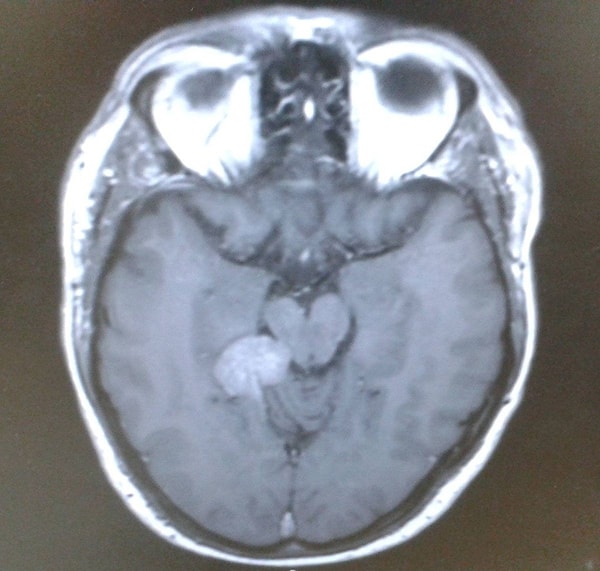

Two years after his initial diagnosis, Darren was directed by his doctors to undergo a standard hearing test. Subsequent advanced examinations and MRI scans revealed that he was harboring a slowly growing, low-grade tentorial meningioma at the base of his brain.

This advanced technology treatment was aimed at obliterating tumor cells while sparing healthy tissues. Thanks to a metal frame affixed to his head during the procedure, the tumor was mapped in three dimensions and targeted with pinpoint precision using radiation. The treatment was successful, yet Darren continues to grapple with neurological side effects such as epilepsy, vision impairments, and tingling on his left side. Moreover, he underwent numerous cardiac procedures due to heart rhythm abnormalities and consequently lost his driving license.